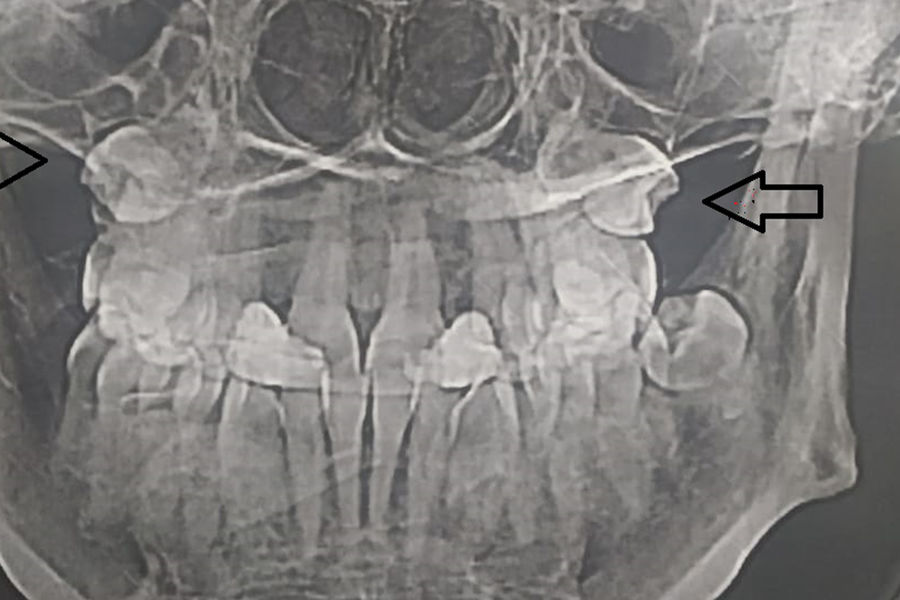

Жительница Самары обнаружила, что в гайморовых пазухах у нее выросли зубы, сообщает ГТРК «Самара».

Об этом женщина узнала, сделав МРТ. Выяснилось, что «четверки» (зубы которые идут после клыков) выросли вместо челюсти в носу.